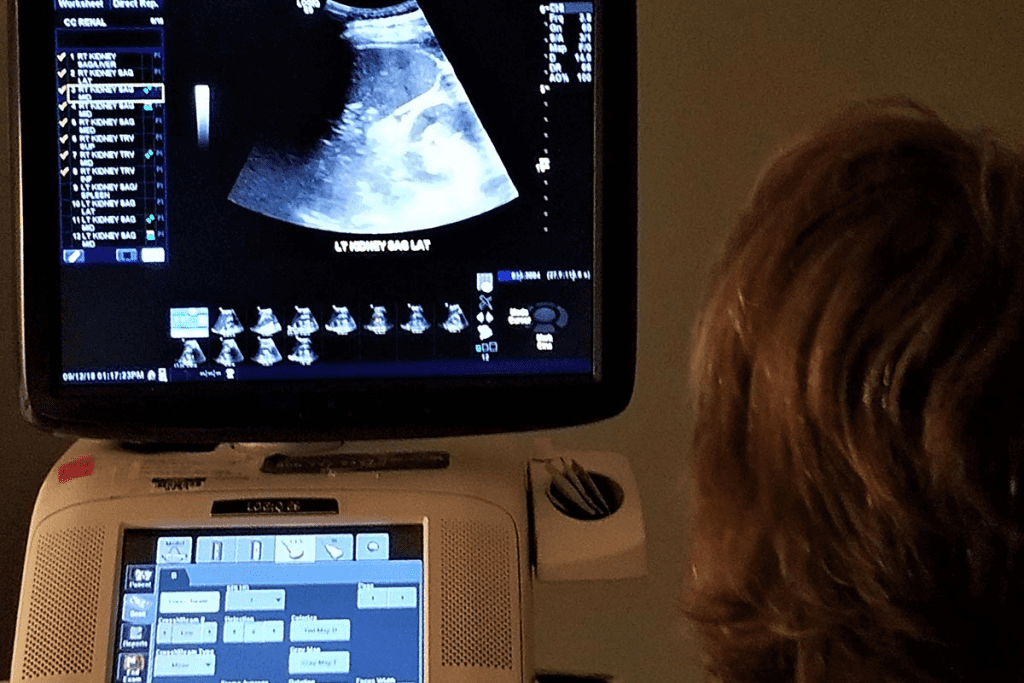

How Bladder Sonography Works

Ultrasound uses sound waves to create detailed images of the bladder. A technician applies gel and uses a transducer to send sound waves. These waves bounce back, showing images of the bladder and any tumors.

Doctors say ultrasound is key because it’s safe and doesn’t use radiation. It’s great for first checks, helping avoid radiation and making it easier for patients.